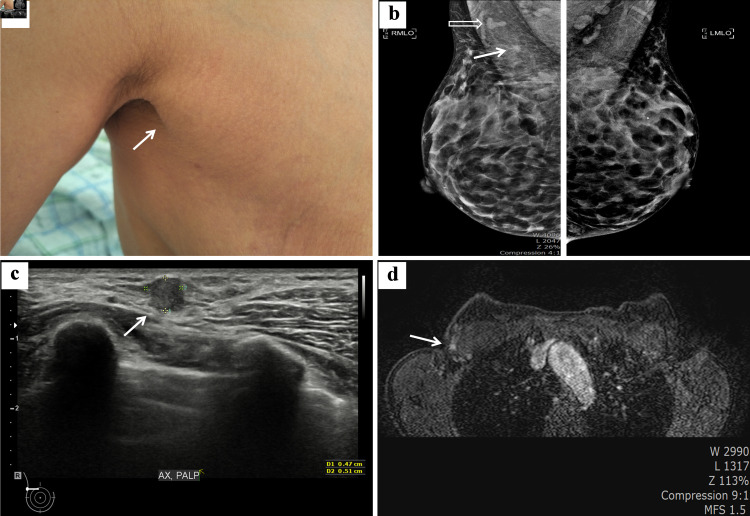

Primary breast cancer occurring in accessory breast tissue is exceptionally rare, with an incidence of 0.2-0.6%. It can aggressively progress, often leading to early metastasis. Treatment is typically delayed due to the rarity, variety of differentials, and lack of clinical awareness of the disease. In axillary surgery, sentinel lymph node mapping in patients with axillary breast cancer is technically challenging and has been poorly described. Here, we present a case of a 53-year-old woman with a 0.5 × 1 cm hard lump in the right axillary region for 2 years, progressive growth for 6 months, and no concomitant breast lesion or axillary lymphadenopathy. Core needle biopsy revealed invasive ductal carcinoma with estrogen receptor and progesterone receptor expression and human epidermal growth factor receptor 2 negativity, whereas mammography and breast magnetic resonance imaging revealed no primary breast lesions. She was diagnosed with invasive cancer arising from an accessory breast and underwent wide total excision of the right accessory breast and sentinel lymph node biopsy. Sentinel lymph node biopsy can be successfully performed using intratumoral dye and subareolar radiocolloid mapping in accessory breast cancer surgery. Axillary accessory breast tissue is outside the scope of the screening breast examination; therefore, oncologists must be aware of this entity and associated pathologies.